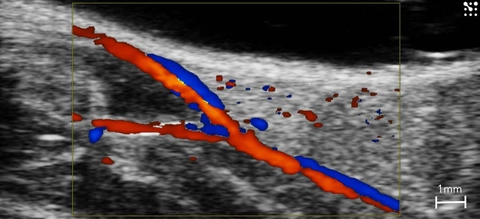

Femoral Artery Bifurcation

Bifurcation of the femoral artery in the mouse seen using color Doppler.